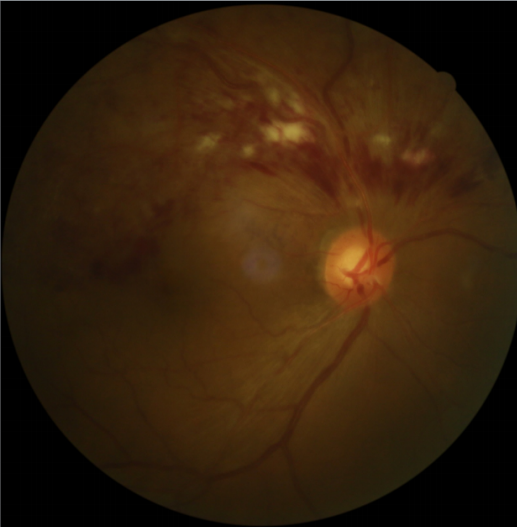

患者刘某,58岁,因右眼视力下降伴变形1月入院。既往有高血压病,血糖偏高病史,左眼视物不见10余年,经过眼科主治医师方霏的详细检查及眼底造影检查,发现是患上了右眼视网膜分支静脉阻塞,右眼黄斑水肿,左眼萎缩性黄斑病变。刘大叔入院时右眼视力仅0.1 ,需要使用一种新型的生物制剂(抗 VEGF)治疗,方霏主治医师向患者及家属交待病情、手术必要性及相关风险 ,在排除了手术禁忌症后,患者及家属表示同意手术治疗。次日,方霏主治医师在患者表面麻醉下进行右眼玻璃体药物注射术,术后患者无明显特殊不适。4周后复查,右眼黄斑水肿明显减轻,视力由0.1提高至0.6。玻璃体腔注药术明显改善了患者视力,患者刘大叔表示十分满意。

术前眼底照相及眼底造影FFA

术后4周眼底照相